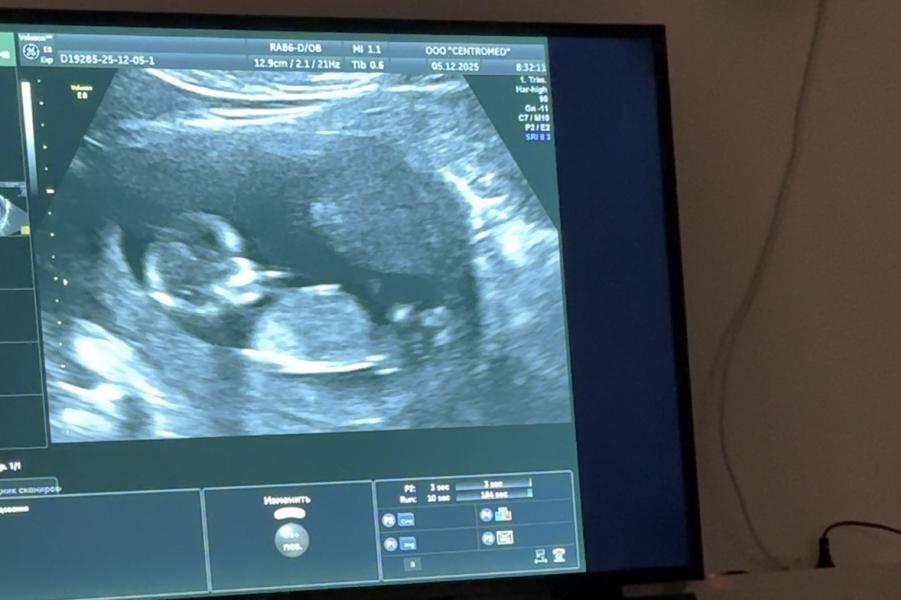

Как определить пол ребёнка по УЗИ: половой бугорок и другие признаки

Ким курдугуй 🩷🩵?😅половой бугорокпут костубэтэх бьлх

На первом фото как девочка, на втором мальчик )

На 12 недель не понятно,тоже долго разгадывала кто😁17 недель уьу точно покажет

Девочка кажется

Девочка бьлах)

Уол курдук😍